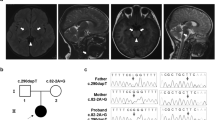

Radiological findings and results of molecular analysis. (a–d) Axial magnetic resonance images examined at 27 years. T2-weighted axial images (a–c) and a fluid-attenuated inversion recovery image (d). (a) In the spinal cord, the posterior columns (yellow) and the lateral corticospinal tracts (red) are involved. (b) At the level of the pons, high signal intensity is shown in bilateral lesions in the pyramidal tracts (red), medial lemniscus (yellow), superior cerebellar peduncles (blue), and intraparenchymal trajectory of the trigeminal nerve (green). (c) At the level of the basal ganglia, the posterior limb of the internal capsule and periventricular white matter are affected. (d) High signal intensity is shown in the periventricular white matter associated with multiple small cysts. (e, f) Electropherograms of Sanger sequencing for the patient, his mother, and the sister. Although a c.228-20T>C polymorphism is shown in both the patient and his sister (e), c.228-15C>G is only present in the patient. c.358_359delinsTC (p.Gly120Ser) is commonly shown in all samples (f), and the affected amino acid is conserved among species (g).

This study was performed in accordance with the Declaration of Helsinki and was approved by the Ethics Committee of Tokyo Women’s Medical University. After obtaining written informed consent, blood samples were obtained from the patient, his mother, and his younger sister. The father’s sample was not obtained, because the couple was divorced. Although LBSL was suspected based on the abovementioned findings, whole-exome sequencing was performed. Briefly, DNA samples were captured using the SureSelect Human All Exon Kit v5 (Agilent Technologies, Santa Clara, CA) and sequenced on an Illumina HiSeq 2500 system (Illumina, San Diego, CA) with 101 bp paired-end reads. Exome data processing, variant calling, and variant annotation were performed as previously described.9 The average read depth of protein-coding regions ranged from 87.29 to 118.99×(mean coverage against coding regions: 118.99×(proband), mother: 87.29×(mother), 87.76×(sister)), and at least 91.2% of target bases were sequenced with 10 or more reads for each sample (96.5% (proband), 91.2% (mother), and 92.5% (sister)). Common single-nucleotide polymorphisms with minor allele frequencies ⩾1% in dbSNP 135 and variants observed in more than five subjects of our in-house exome database (n=575 controls) were filtered out. We evaluated the remaining variants using SIFT (http://sift.jcvi.org/) and Polyphen-2 (http://genetics.bwh.harvard.edu/pph2/) prediction software. Particular attention was given to mutations found in genes known to cause neurodegenerative diseases when mutated. The samples from the mother and the sister were used for filtering. Finally, two heterozygous mutations in DARS2, NM_018122.4: c.228-15C>G and c.358_359delinsTC (p.Gly120Ser) remained, and mutations in the other candidate genes for leukoencephalopathy were ruled out. p.Gly120Ser was detected in the mother and healthy sister (Figures 1e and f). Although p.Gly120Ser has never been reported previously (Supplementary Table S1), the affected codon is conserved among species (Figure 1g) and prediction scores including SIFT and Polyphen-2 suggested that this mutation is ‘damaging.’ Therefore, we concluded that this mutation is pathogenic. On the other hand, the other mutation, c.228-15C>G, has been reported previously as a pathogenic splicing mutation that causes predisposition to p.R76SfsX5. As this splicing mutation was not detected in the mother and healthy sister, this was suspected to be inherited from his father or to be a de novo mutation. From these findings, we concluded that LBSL features in this patient are derived from compound heterozygous mutations in DARS2.